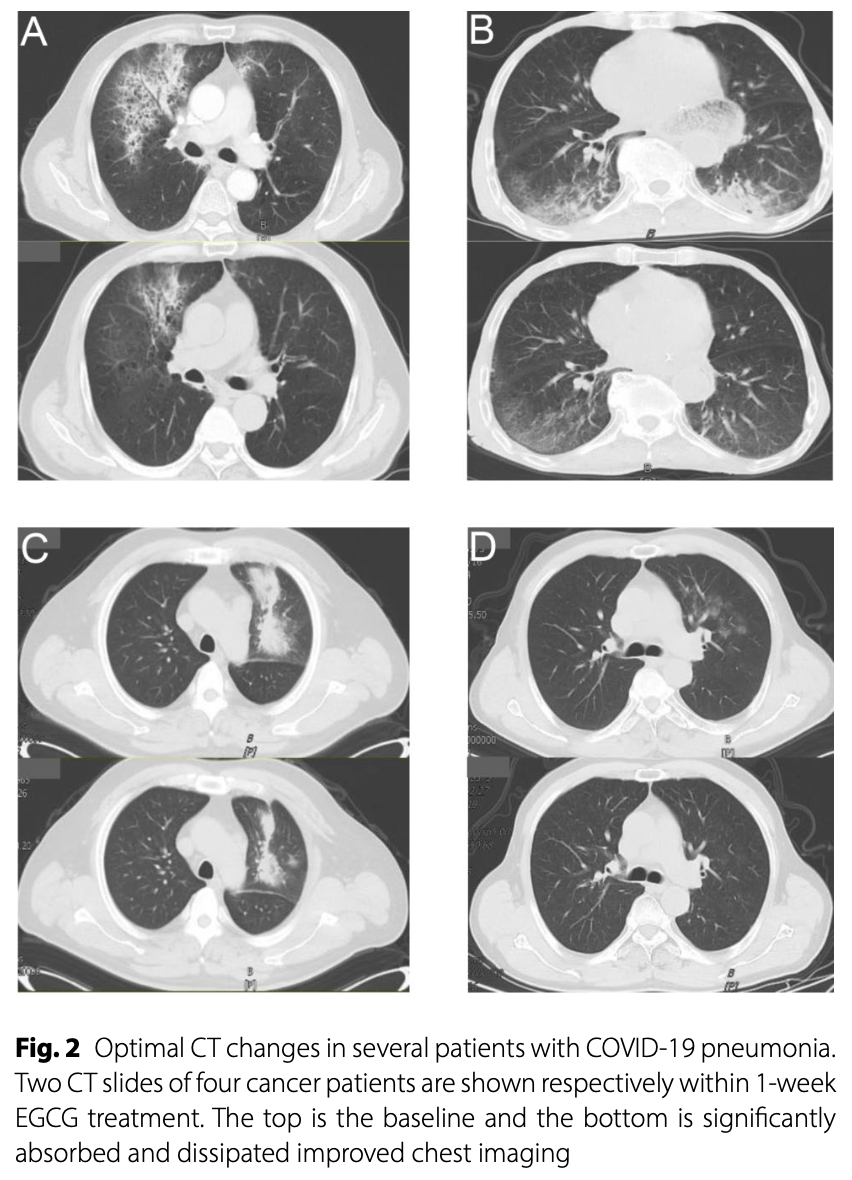

Phase I/II trial of EGCG nebulization inhalation in 54 COVID-19 pneumonia patients with cancer showing good tolerability and improvement in CT scans in 56% of patients after 7 days, with non-progression of pneumonia in 82% of patients. There was no significant difference in inflammation-related laboratory parameters before and after treatment. The maximum tolerated dose was 5878 μmol/L.

Background The antiviral drug Nirmatrelvir was found to be a key drug in controlling the progression of pneumonia during the infectious phase of COVID-19. However, there are very few options for effective treatment for cancer patients who have viral pneumonia. Glucocorticoids is one of the effective means to control pneumonia, but there are many adverse events. EGCG is a natural low toxic compound with anti-inflammatory function. Thus, this study was designed to investigate the safety and efficacy of epigallocatechin-3-gallate (EGCG) aerosol to control COVID-19 pneumonia in cancer populations. Methods The study was designed as a prospective, single-arm, open-label phase I/II trial at Shandong Cancer Hospital and Institute, between January 5, 2023 to March 31,2023 with viral pneumonia on radiographic signs after confirmed novel coronavirus infection. These patients were treated with EGCG nebulization 10 ml three times daily for at least seven days. EGCG concentrations were increased from 1760-8817umol/L to 4 levels with dose escalation following a standard Phase I design of 3-6 patients per level. Any grade adverse event caused by EGCG was considered a dose-limiting toxicity (DLT). The maximum tolerated dose (MTD) is defined as the highest dose with less than one-third of patients experiencing dose limiting toxicity (DLT) due to EGCG. The primary end points were the toxicity of EGCG and CT findings, and the former was graded by Common Terminology Criteria for Adverse Events (CTCAE) v. 5.0. The secondary end point was the laboratory parameters before and after treatment. Result A total of 60 patients with high risk factors for severe COVID-19 pneumonia (factors such as old age, smoking and combined complications)were included in this phase I-II study. The 54 patients in the final analysis were pathologically confirmed to have tumor burden and completed the whole course of treatment. A patient with bucking at a level of 1760 umol/L and no acute toxicity associated with EGCG has been reported at the second or third dose gradients. At dose escalation to 8817umol/L, Grade 1 adverse events of nausea and stomach discomfort